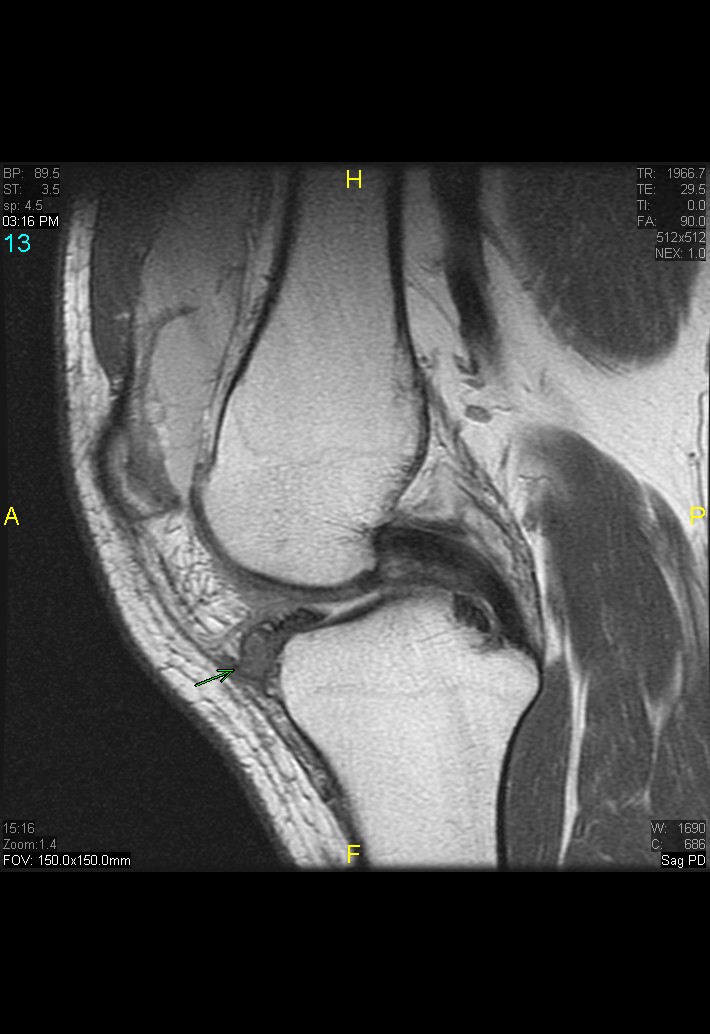

Figure 2 for case gout arthritis ( RID3567 )

Figure 2